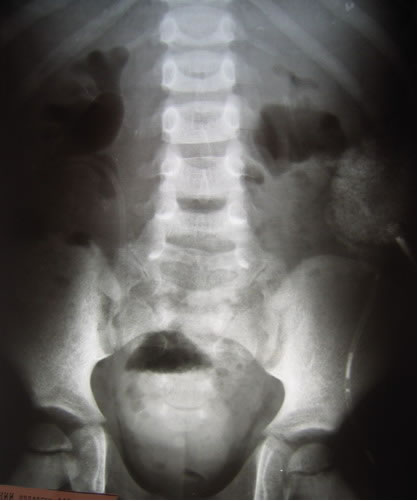

Антеградная уретерография слева